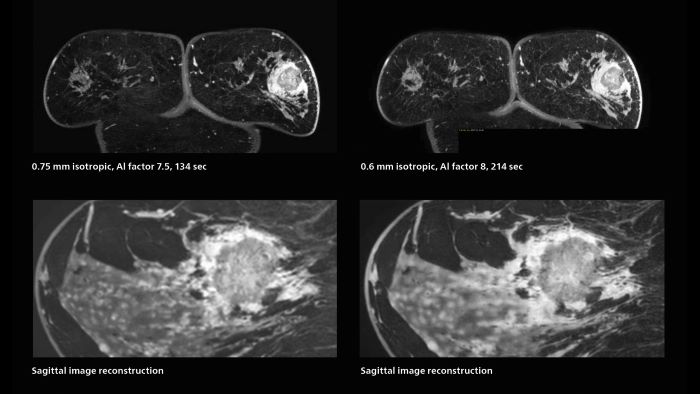

3D MRI of breast cancer

Scanning was performed with two different voxel sizes. AI enabled volume MRI allows image reconstruction in other directions. Biopsy revealed invasive ductal carcinoma in this patient. Performed on Elition X.

Fast AI-enabled MRI of breast cancer: comparing 3D acquisitions with 0.75 mm and 0.6 mm isotropic voxels.

Speed and high image quality are also important factors determining the diagnostic value of breast MRI. “When the spatial resolution is not high enough for making the diagnosis of breast cancer, a very difficult decision must be made,” says Dr. Katahira. “Since SmartSpeed now allows us to increase the resolution, we can often easily provide a confident answer. In the past with SENSE we used 1.2 mm isotropic voxels in breast imaging after contrast admission. With Compressed SENSE that is 0.8 mm. Now with SmartSpeed we can acquire 0.6 mm isotropic voxels and the images are so clear that even tiny details are clearly visible.”

“The use of SmartSpeed has considerably improved our breast cancer imaging, with higher temporal resolution, higher spatial resolution, and higher SNR compared to the past, when we were using just Compressed SENSE. In addition, the dynamic study is now more useful in diagnosis because the ultrafast dynamic scan can be taken every 3 seconds.”

• ExamCard for 0.7 mm isotropic, 2:09 min, acceleration factor 7.5

• ExamCard for 0.6 mm isotropic, 3:37 min, acceleration factor 8